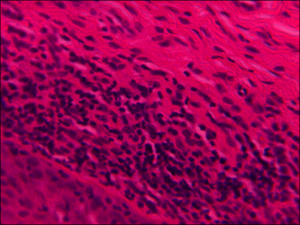

病理組織学的所見

lichen planus(扁平苔癬)

上皮に、明らかな異型は見られず、上皮直下に帯状のリンパ球浸潤を認めます。一部、基底側の細胞で空胞変性が見られます。基底膜部には好酸性、PAS陽性の変性物が見られます。P53、Ki-67免疫染色では腫瘍性変化を示唆する明らかな所見はありません。またPAS染色、グロコット染色で陽性を示す菌体は見られません。以上より、口腔扁平苔癬を考えます。

![]() HE染色 強拡大像 (拡大倍率 400倍) |